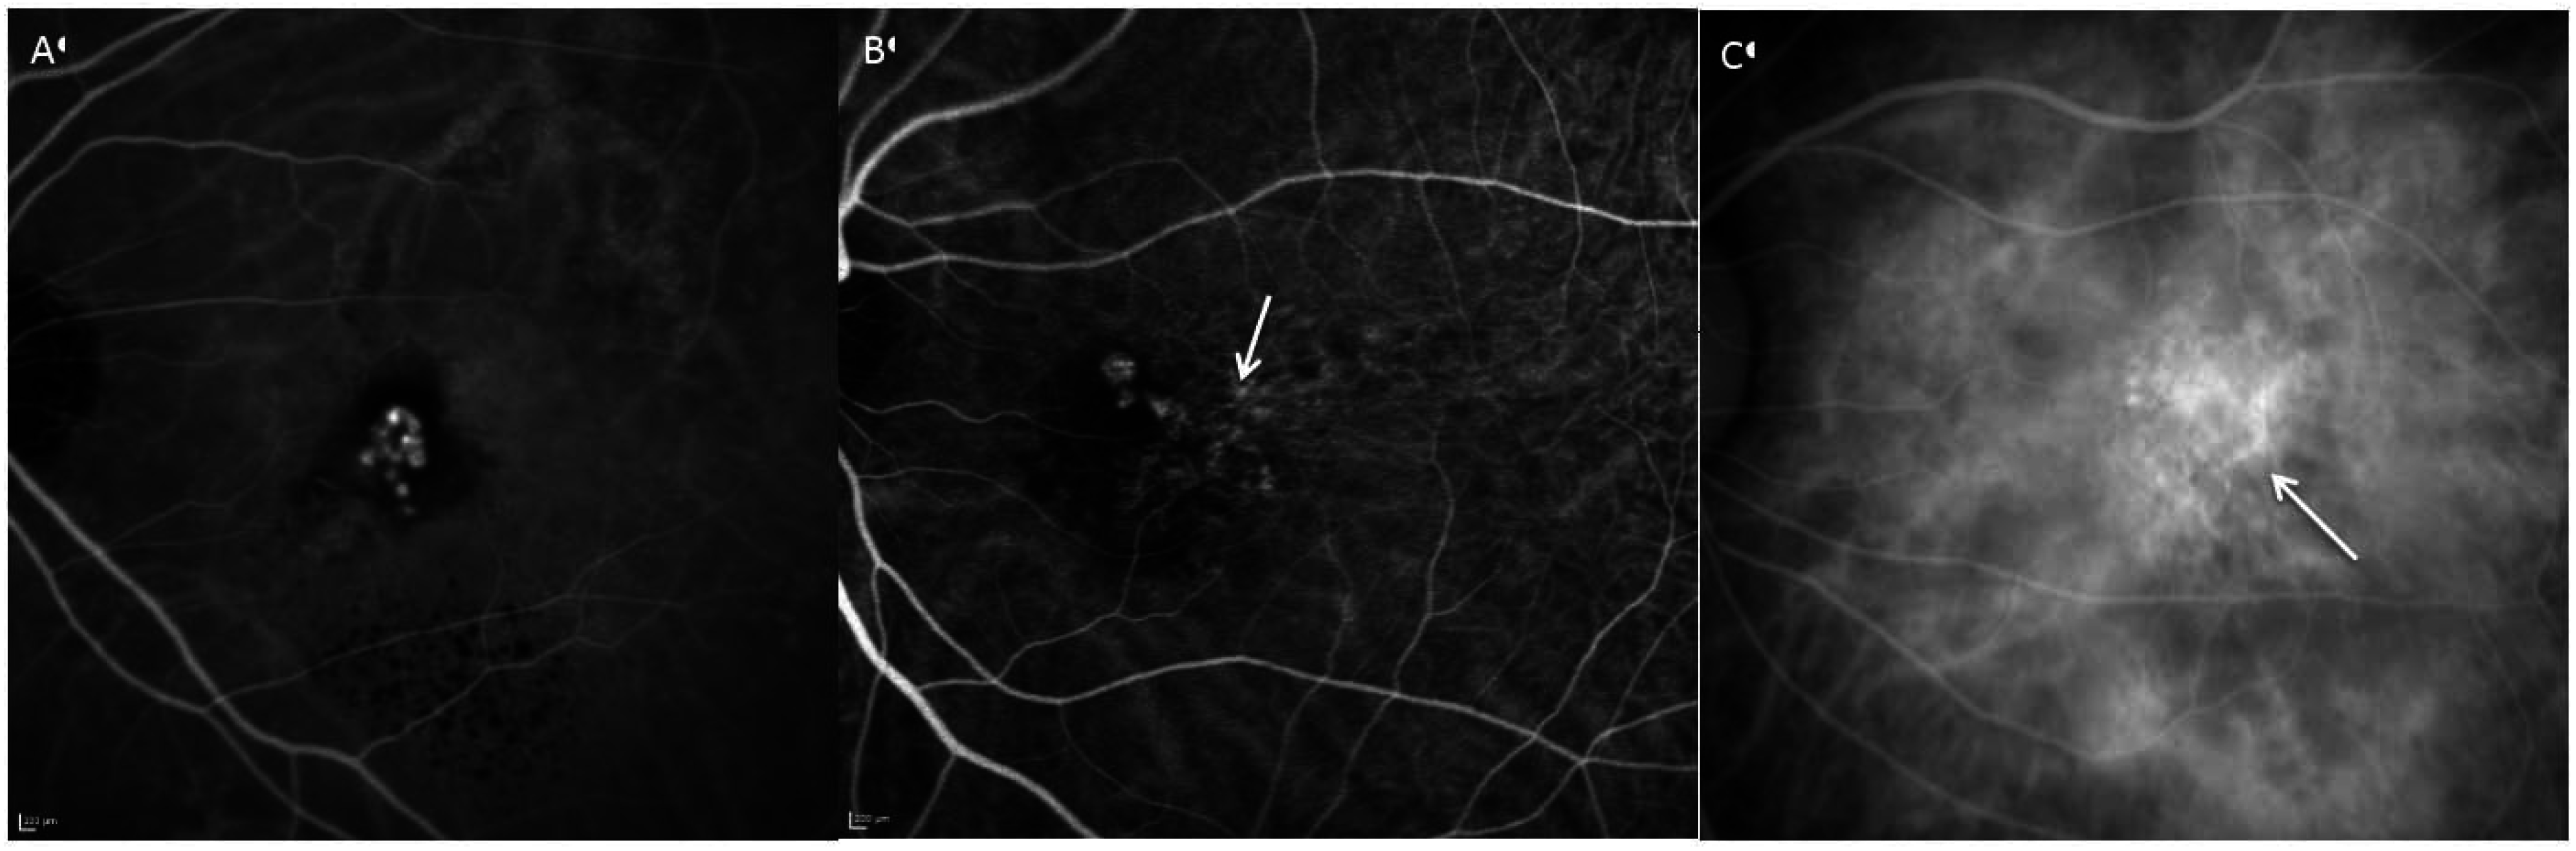

6. Angiography

7. Fundus Autofluorescence